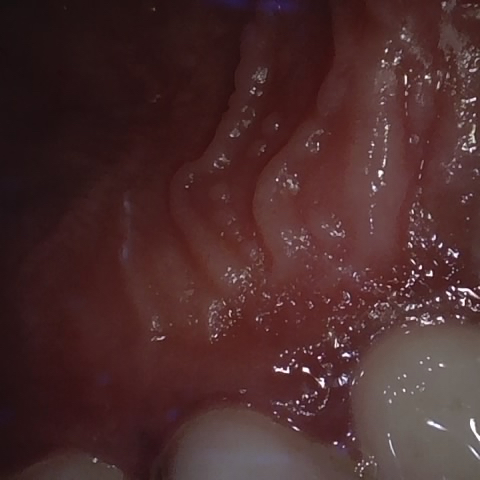

Image 734 / 1103

NHD39174

Annotated as "Good"

Original Image Rendering Image